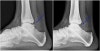

X-ray에서 경골 전방 가장자리, 거골 활차부 전방 가장자리에 외골종 양상의 골 증식 변화가 나타날 수 있습니다.

X-ray : 발목 충돌증후군(Posterior impingement)